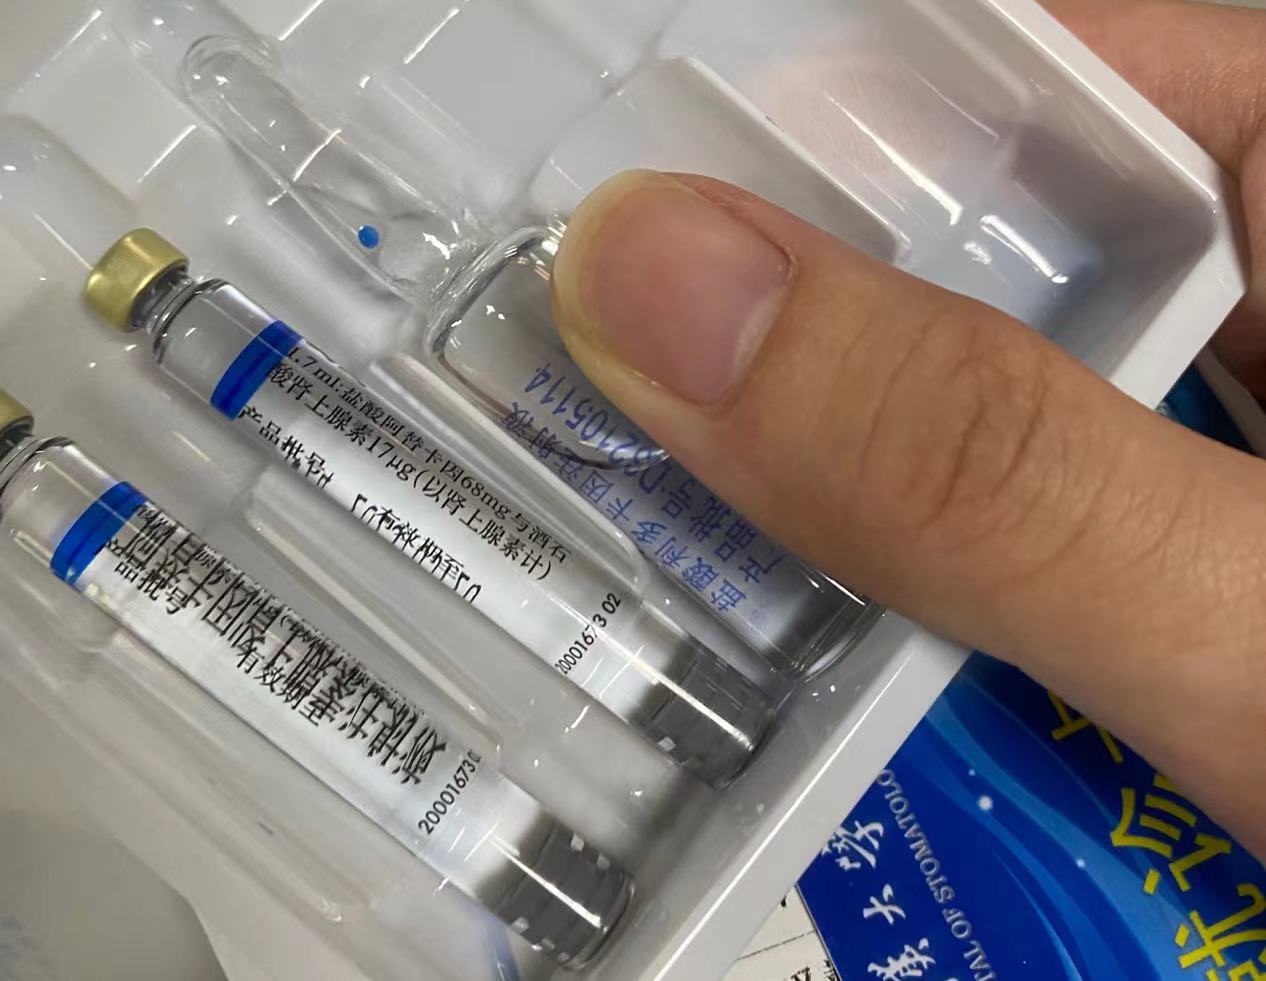

去挂了武大口腔的颌面外科刘国胜教授的号,先是他的学生看了看我的牙和片子,问我先拔哪一颗,一次只能拔一边。于是我斩钉截铁地说:“中间那一颗最难的!”,于是缴费,2500 大洋好贵,到前台拿麻药,等待进手术室。

可能是我去的比较早的原因,等了一会儿医生就把我带进手术室了,打麻药也是刘教授的学生,小姐姐很温柔,打麻药还好,就一点疼,麻药打好过后,刘教授进来了开始拔牙了,只见他拿起手术刀,我也看不见口内,只能猜他是在划开牙龈,再就是那种类似电转的东西,只能听见轰轰的声音,应该是划开骨头,到了后来教授弄了半天也没弄下来,问我疼不疼,我感觉到有一点,于是加了一管麻药,我感觉当时眼泪都快留下来了,后来他拿起锤子,他和他的学生一起锤我的上颚,我害怕地闭紧眼睛,没过一会儿,他就从我的口内取出了牙齿,然后放上了胶原蛋白,说是好让我长骨头,最后缝针,我数了下大概缝了五针左右的样子,大概用了一个小时我才出手术室,一直张开口的动作让我也很累。